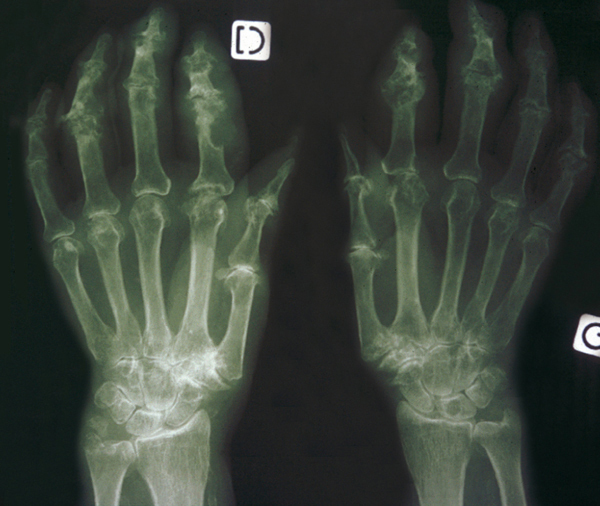

© Gérard Chalès, Pascal Guggenbuhl (La Revue du Praticien)

Radiographie de mains (face). Goutte : opacité des parties molles (tophus), destruction des interphalangiennes proximales et distales. Voir : Chalès G, Guggenbuhl P. Arthropathie microcristalline. Rev Prat 2013;63(5):709-20.